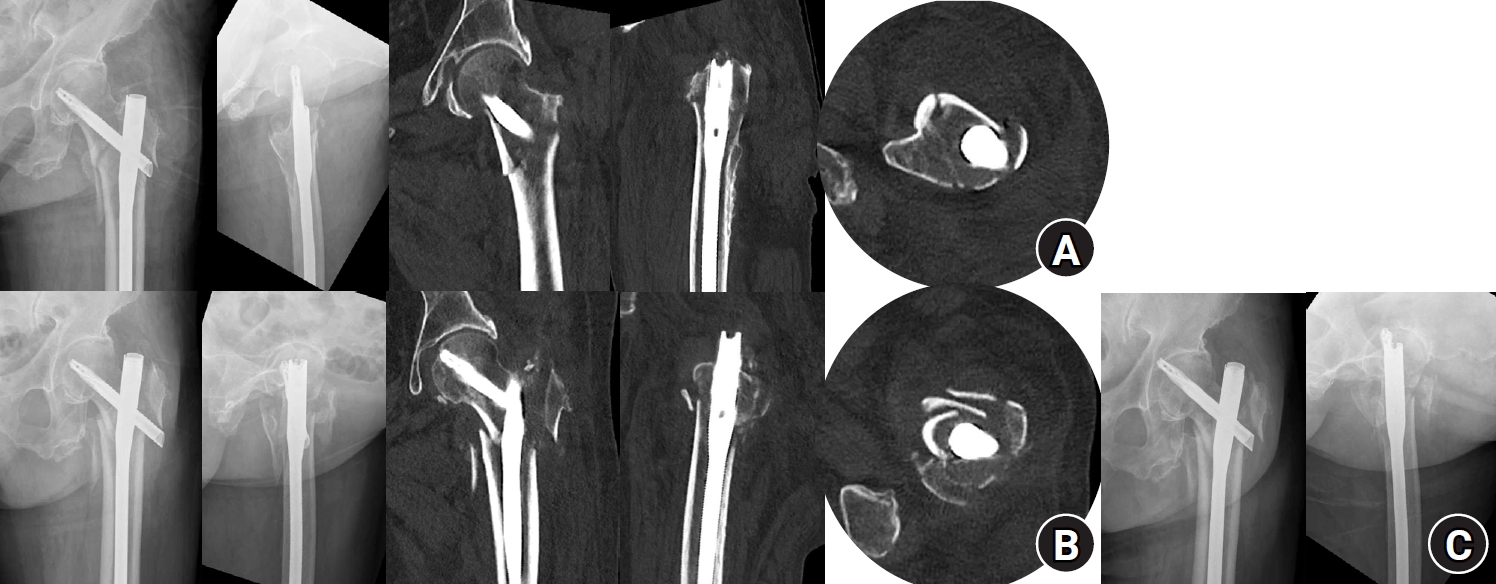

Fig. 3.

Radiographic, fluoroscopic, and computed tomography (CT) images from an 83-year-old female patient with a left femoral intertrochanteric fracture (AO/OTA classification A3). (A) Preoperative plain radiographs and CT showing a negative anteromedial cortical support (AMCS) state; (B) Intraoperative fluoroscopic images illustrating the percutaneous anterior leverage technique; (C) Comparative postoperative images from plain radiographs and CT showing that lateral plain radiographs alone do not clearly reveal the AMCS state. This CT shows positive AMCS in both the coronal and axial views; (D) Plain radiographs obtained 3 months postoperatively, showing bone union without complications.

jmt-2025-00311f3.jpg